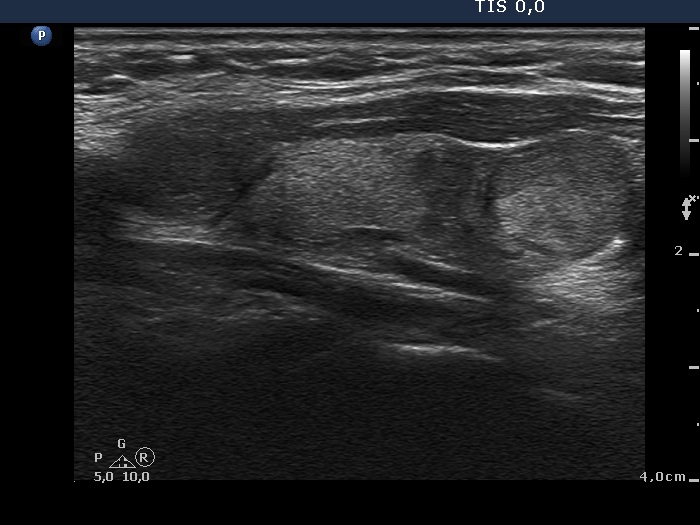

The borders of the nodule - case 1527 (ultrasonographic picture 5)

Right lobe, longitudinal scan

Another longitudinal scan of the right lobe. Note the lobulated margins of the hypoechogenic lesion.